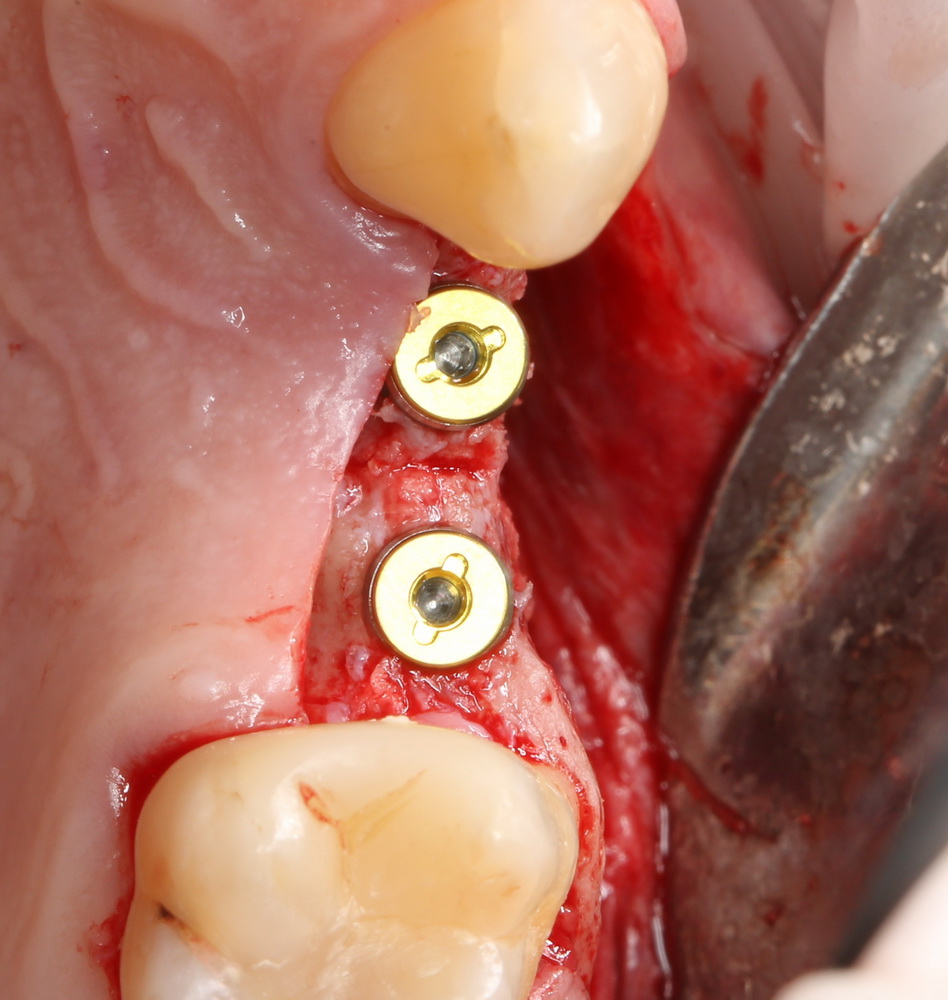

Что же касается нерезорбируемых мембран… Было дело, работал с Gore-Tex (дорого, очень дорого), титановыми сетками (заколебался потом доставать) и тефлоновыми Cytoplast:

результат:

или

с трудом выковыриваем сетку и ищем имплантат:

чтобы поставить формирователь:

Ну а, в целом же, не считая небходимости ОБЯЗАТЕЛЬНОЙ фиксации пинами или винтами, работа с нерезорбируемыми мембранами не отличается от работы с резорбируемыми коллагеновыми материалами. Поэтому особых преимуществ, способных повлиять на результаты лечения, у нерезорбируемых мембран нет.